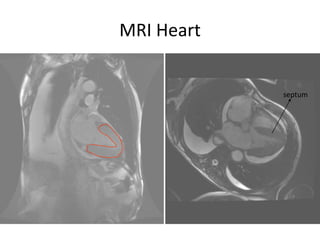

SCREENING FOR CARDIAC AMYLOIDOSISSerum Free Light ChainsFree kappa – 530  mg/LFree lambda – 16Increased k:l ratio (33.13)Urine – 950mg/24h of albumin Cardiac MRI scan with Gadolinum

MRI Heartseptum